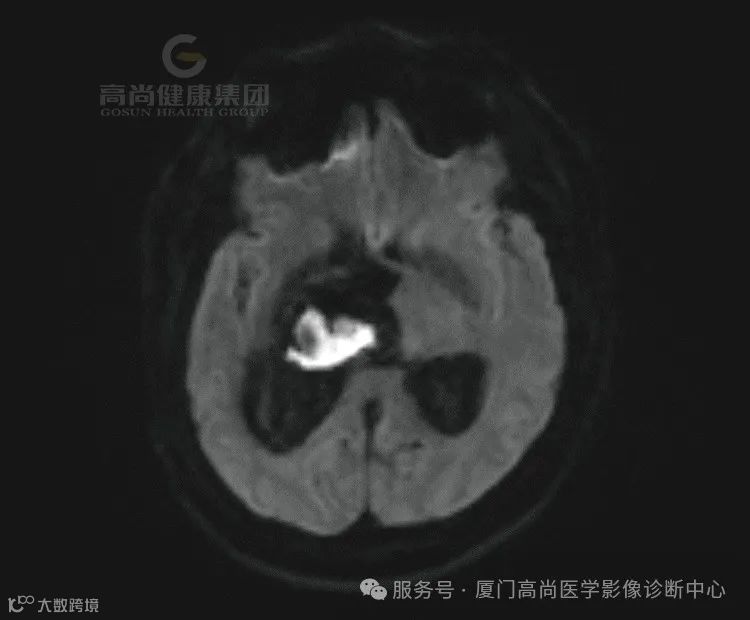

患者代诉左侧肢体无力半月余,既往高血压史。

1.右侧丘脑、基底节、放射冠区病灶,考虑脑出血(亚急性期)并破入右侧脑室,中线结构局部左偏,请结合临床。

(1)亚急性早期(3-6d):血肿中心在T1呈等信号,外周呈高信号,且高信号逐渐向中心扩展;在质子加权和T2呈低信号。

(2)亚急性晚期(1-4周):T1和T2上均呈高信号,灶周水肿,占位效应逐渐减轻。